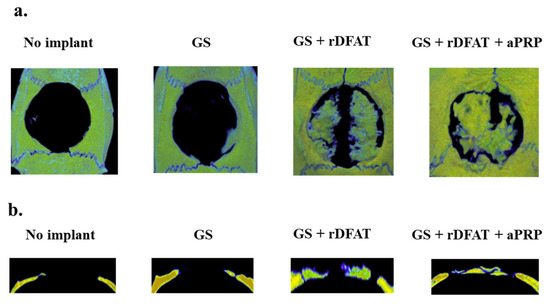

3.6. Bone Formation in a Rat Calvarial Defect Model

3.7. Pathological Evaluation